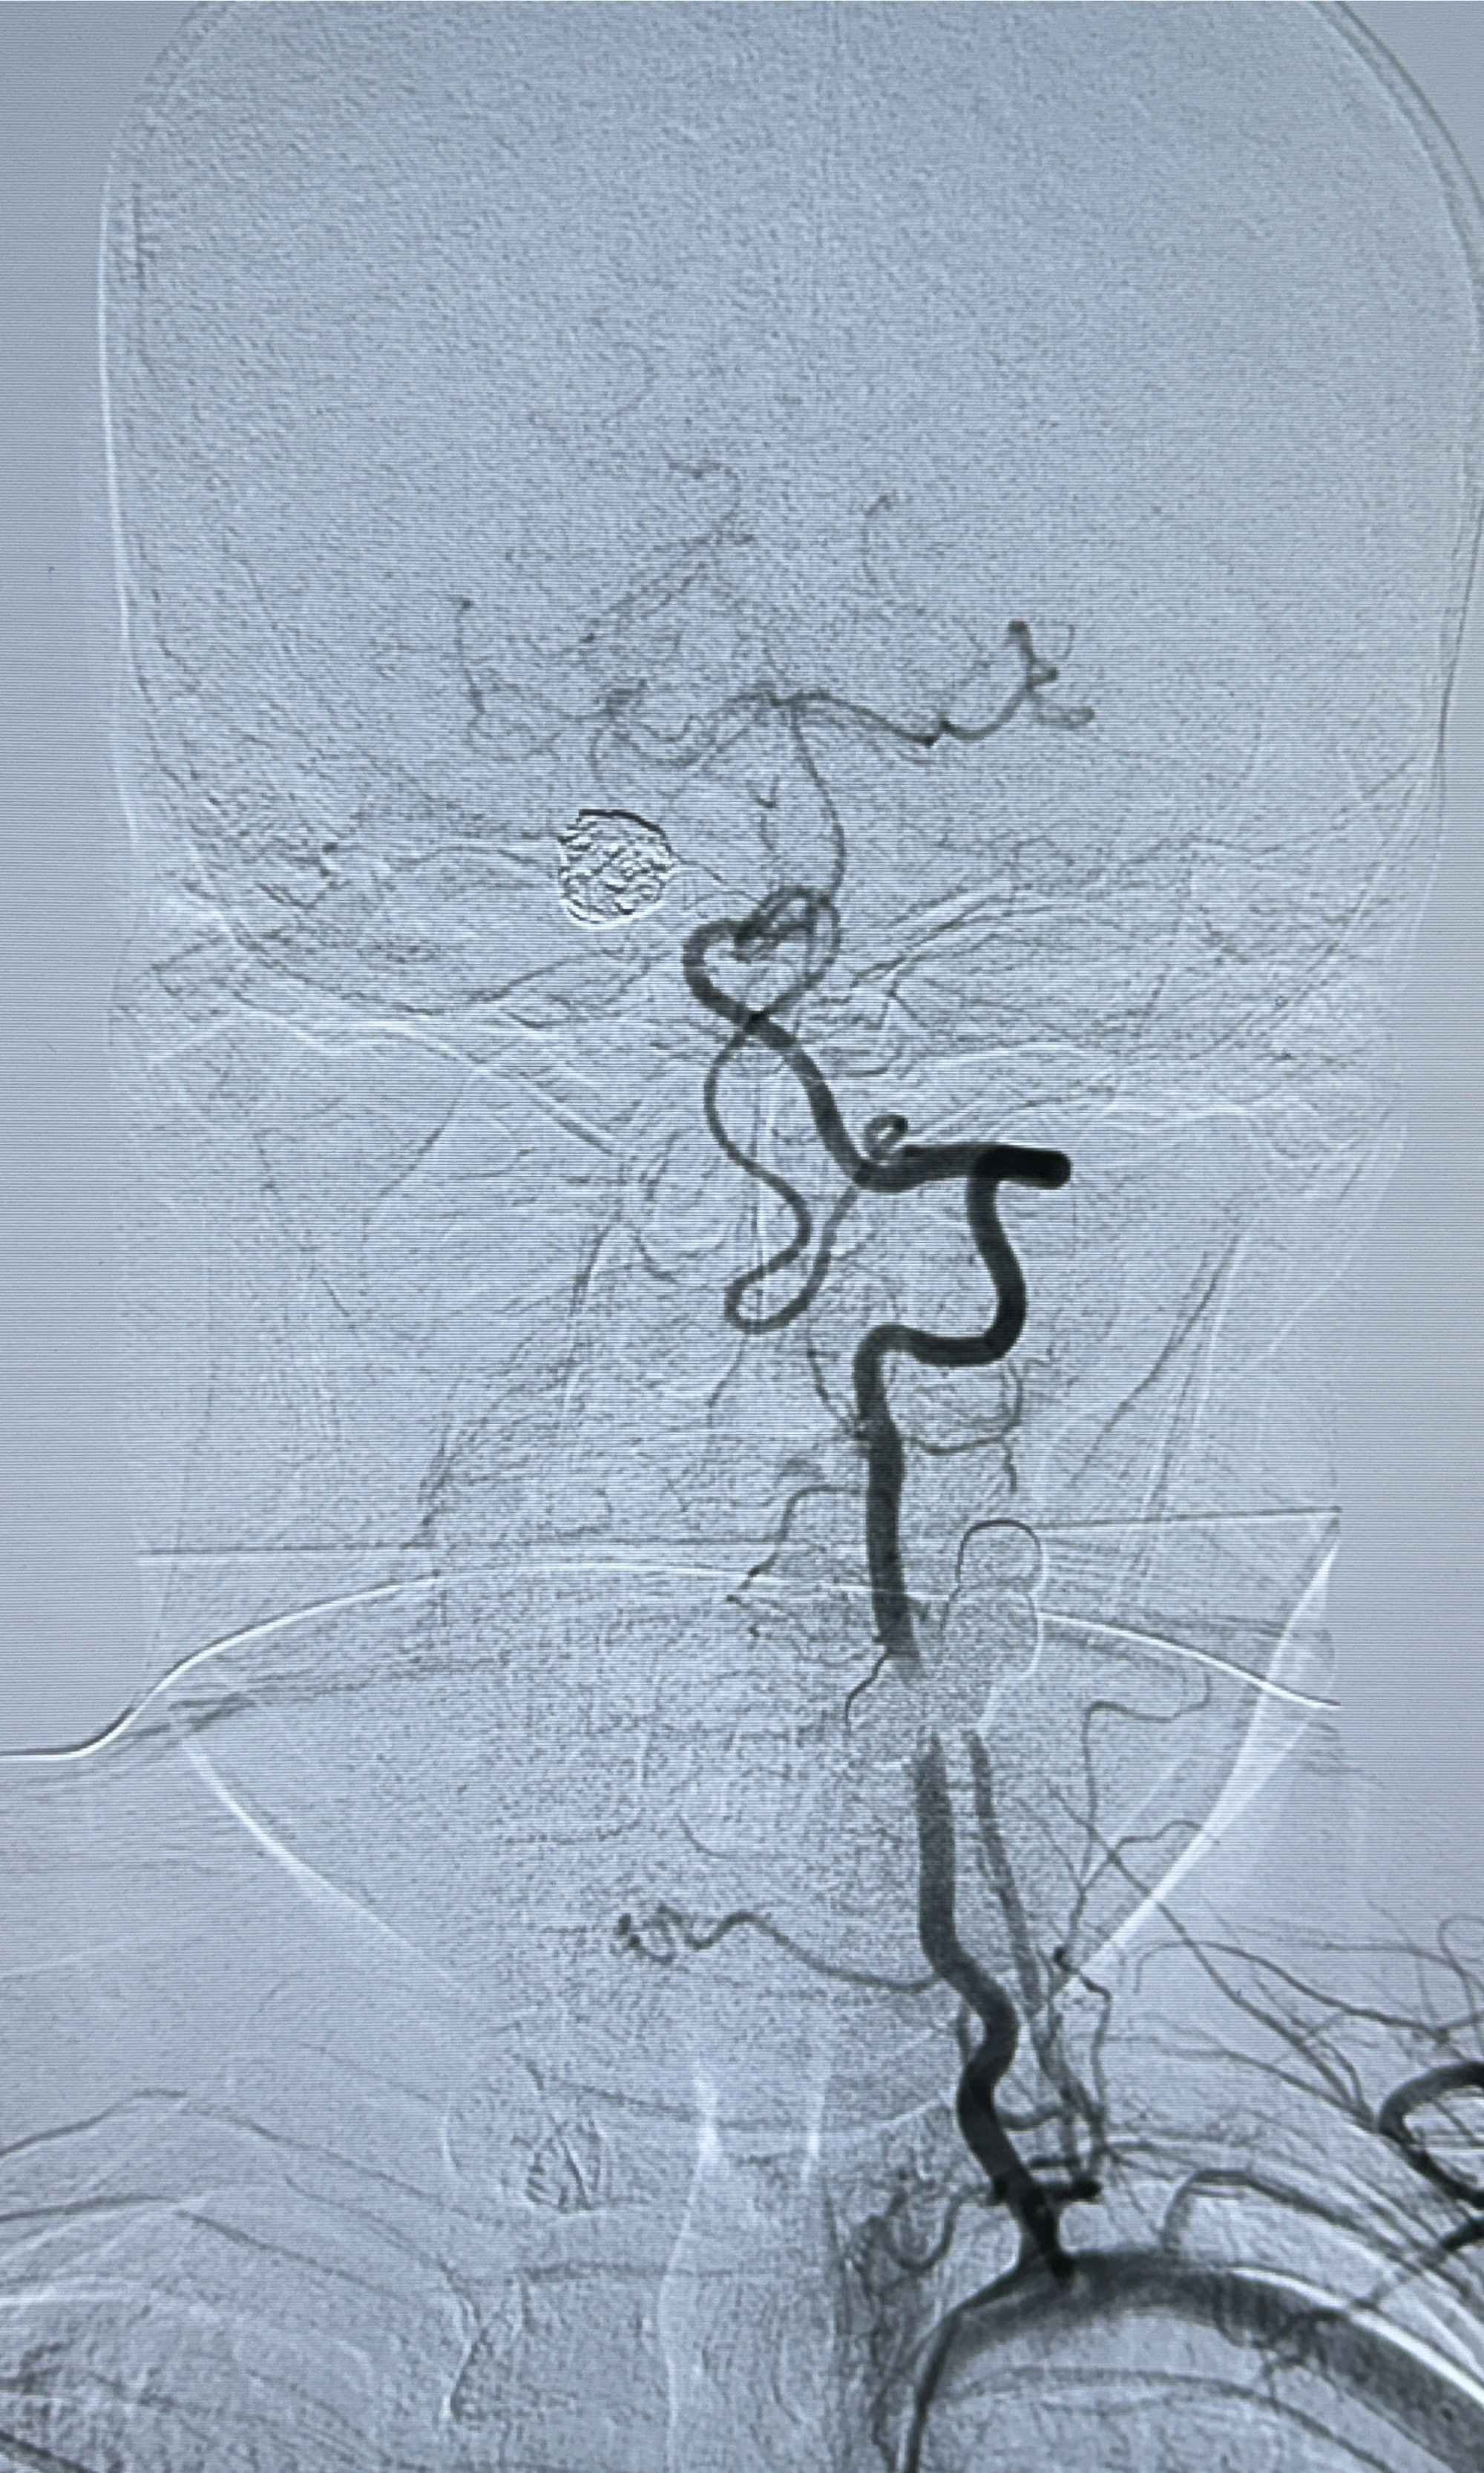

现病史:患者诉2022.06.24因“检查发现颅内动脉瘤”就诊于华山医院查全脑血管造影诊断右侧椎动脉夹层动脉瘤(14.86*12.02mm),随后在全麻下行支架辅助栓塞术(LEO,本人诉2枚支架),术顺,术后予以阿司匹林、氯吡格雷、阿托伐他汀钙片对症治疗;术后3月因下肢淤青停用氯吡格雷,患者近2月开始出现发作性右侧枕部隐痛不适,持续时间约几分钟,着凉可诱发,余一般情况可,目前服用阿司匹林1片qd治疗中,为复查脑血管造影收入我科。

2024-01-08DSA:右侧椎动脉V4段夹层动脉瘤双支架辅助弹簧圈栓塞术后

患者支架辅助治疗后18个月,动脉瘤痊愈